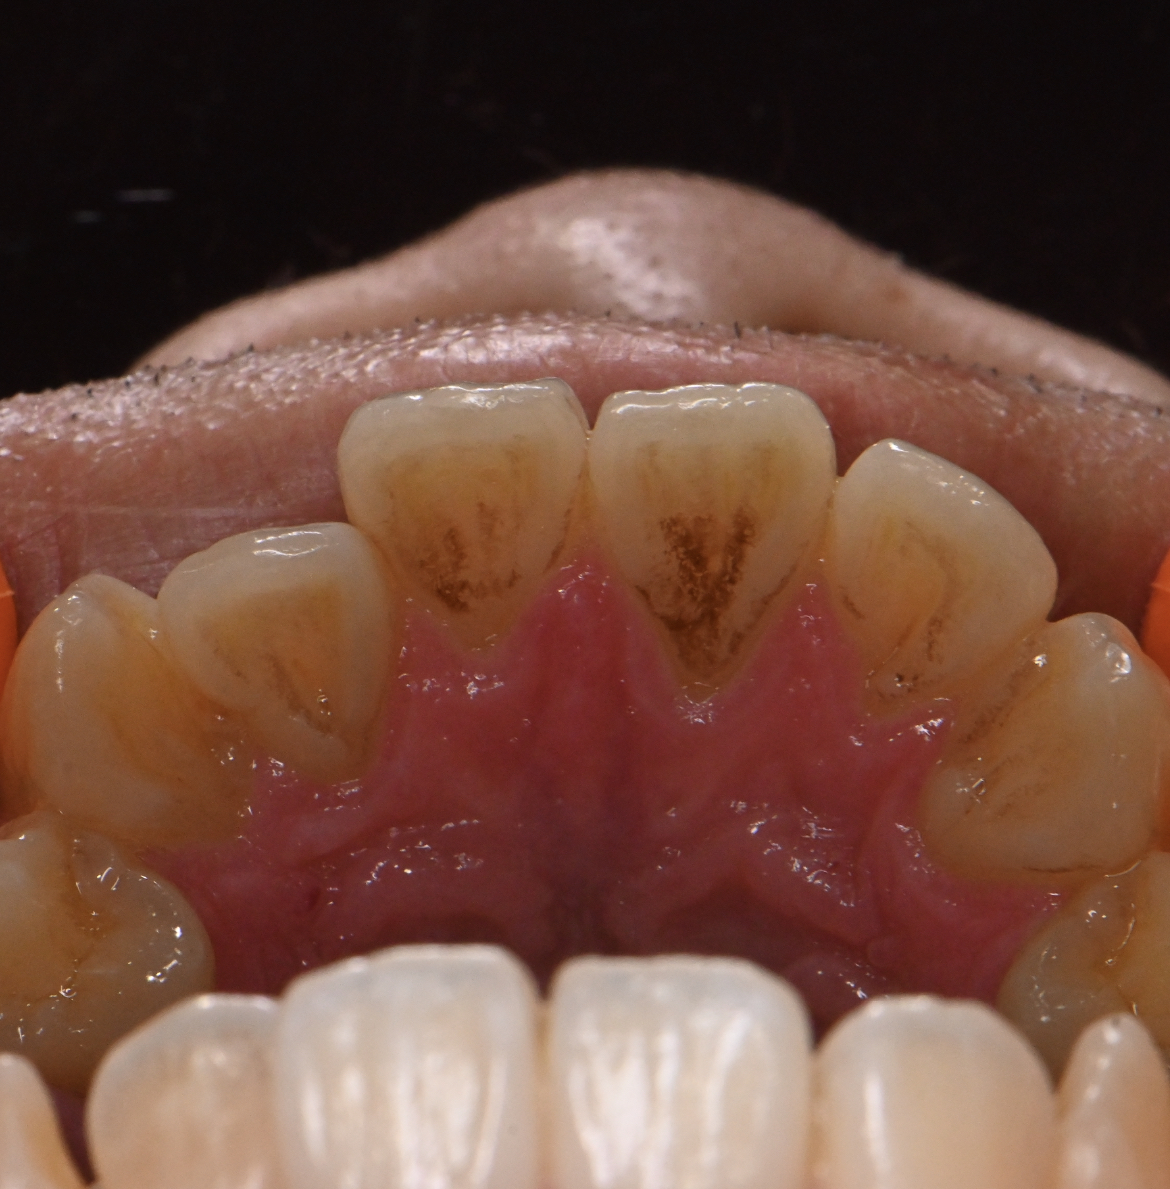

今回は矯正が終わり固定がついているところに着色が付着してしまった方と、コーヒーを高頻度で飲む方にエアフローをしきれいにさせて頂きました?✨

1.矯正後の固定ワイヤー部に着色がついてしまってる方

2.コーヒーを高頻度飲む方

着色はエアフローで綺麗に落とせますが歯の黄ばみはエアフローで落とせないのでホワイトニングでご自身の歯を白くする形になります。